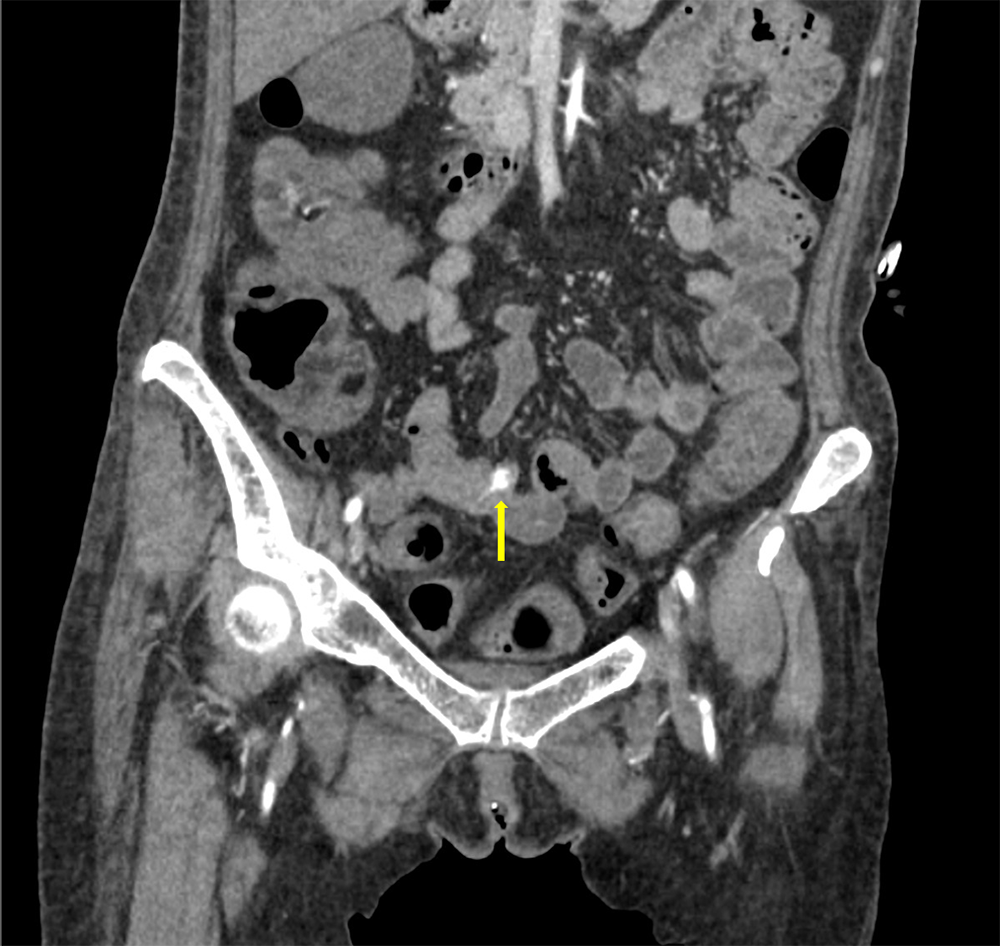

サイトメガロウイルス感染症を背景に下血がみられ消化管出血が疑われた。出血源の精査目的に造影CTが施行された。造影CTにて回腸で造影剤の血管外漏出像がみられ、出血源と考えられた。

造影CT撮像後、直ちに経カテーテル的血管塞栓術を施行し原因血管を金属コイルで塞栓し止血を得ることができた。